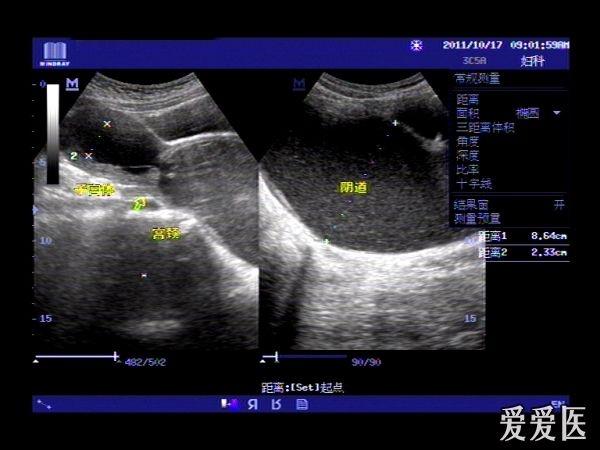

患者,女,14岁,因周期性下腹部胀痛不适3月余来我院就诊。查体:下腹部可扪及一包块。超声检查膀胱适度充盈,子宫前倾位,宫底部上移至脐平面,宫体宫腔,宫颈及**明显扩张呈椭圆形,内回声不纯净,呈细密的点状回声,宫内膜显示清晰。超声诊断处女膜闭锁